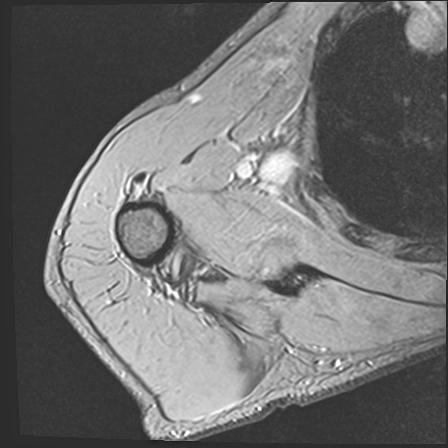

60058 3/9 11/4 右肩 2R+MRI 73歳男性 肩腱板損傷